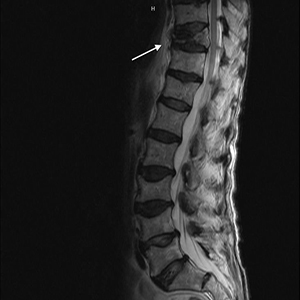

• Hernias discales (lumbociática)